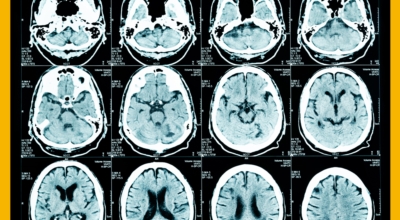

뇌조직은 평소에도 다량의 혈류를 공급받고 있는데 어떤 여러가지 원인으로 인해서 뇌혈관에 이루는 관이 막히는 경우 뇌에 공급되는 혈액량이 떨어지면서 뇌조직이 기능을 제대로 하지 못하게 되는데 이렇게 뇌혈류 감소가 일정 시간 이상 지속되다 보면 뇌조직의 괴사가 시작되어 회복 불가능한 상태가 되는데 이를 뇌경색이라 해요. 오늘 알아볼 질병은 뇌경색 초기증상이예요.

뇌경색의 경색이란 허혈성 괴사를 말해요. 여기서 허혈이란 혈관이 막히는 것을 말하고 괴사는 말 그대로 일부가 죽는 것을 말하는데 뇌경색의 경우 뇌의 혈관이 막혀 뇌세포 일부가 죽는 걸 의미해요. 뇌혈관이 막혔다 해서 혈액 공급이 안되는것은 또 아니에요.